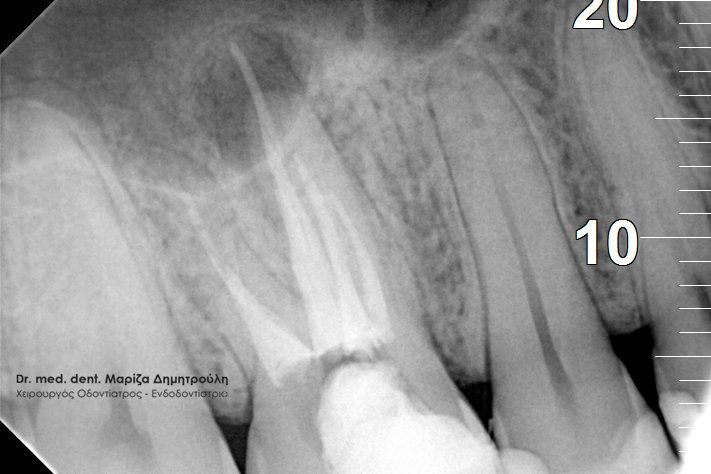

ΠΡΙΝ ΜΕΤΑ

Στον παραπάνω ασθενή έγινε επανάληψη απονεύρωσης και εντοπίστηκε και τέταρτος ριζικός σωλήνας, ο οποίος δεν είχε βρεθεί στην πρώτη ενδοδοντική θεραπεία.